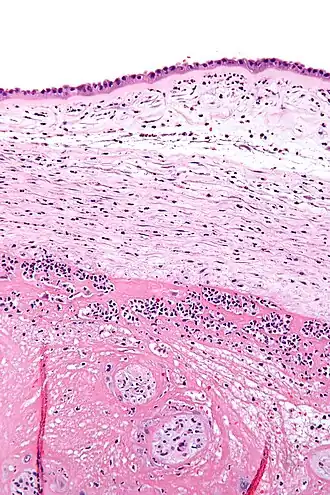

![]() Micrografía mostrando corioamnionitis. Los acúmulos de manchas azules corresponden a células inflamatorias. Tinción hematoxilina-eosina. | ||